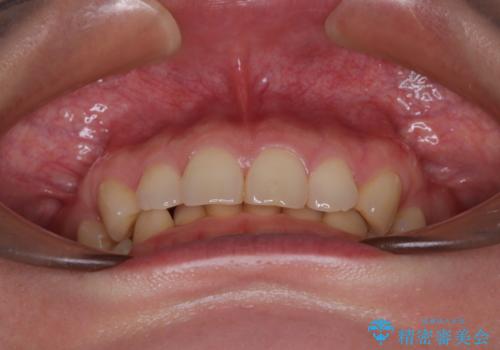

- 下顎前歯が完全に隠れてしまっていることを気にして来院された患者様です。

下顎の臼歯が手前に傾斜していることで咬み合わせが深くなってしまい、下顎前歯が見えないほどに上顎前歯が覆い被さっている状態でした。